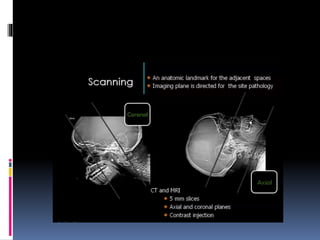

CT NOSE AND PNS

BASIC CONCEPTS

 CT scans typically obtained for visualizing the

paranasal sinus should include coronal and axial (3-

mm) cross

sections.

 Soft tissue and bony windows facilitate evaluation

of disease processes and the bony architecture.

 The use of intravenous contrast material just prior

to scanning can help define soft tissue lesions and

delineate vascularized structures, such as vascular

tumors.

 Contrast-enhanced CT is particularly useful in

evaluating neoplastic, chronic, and inflammatory

processes.

 The CT scan is the GOLD STANDARD

investigation in all preoperative cases as it gives

detailed bony anatomy of the area and serves as

a ‘road map’ for the operating surgeon.

 CT scans are best done after a course of

antibiotics, so that acute inflammation is not

mistaken for chronic mucosal disease.